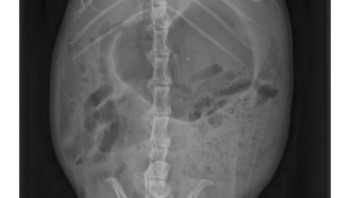

• Hier mal der Vergleich von Johnnys Lunge.

Der wenn man draufschaut linke Lungenflügel war am schlimmsten betroffen.

Oben vor 3 Wochen, unten gestern.

Auf dem ersten Bild fällt der große Unterschied zwischen dem auf dem Bild links zu sehenden Lungenflügel und dem anderen, weniger geschädigten auf. Johnny schien dort nach oder bei dem Einatmen aufgenommen worden zu sein.

Auf dem zweiten Bild schien er gerade ausgeatmet zu haben. Daher ist auch in dem besseren Lungenflügel weniger Luft als vorher. Aber der Unterschied zwischen bei Lungenflügeln ist geringer geworden. Zudem ist auf der auf dem Bild rechten Seite der Lungenflügel wieder gleichmäßiger "befüllt".

Meine Schwester war zur Röntgenbildbesprechung beim letzten Mal da, aber insgesamt sollte deine Beschreibung laut ihr passen😊